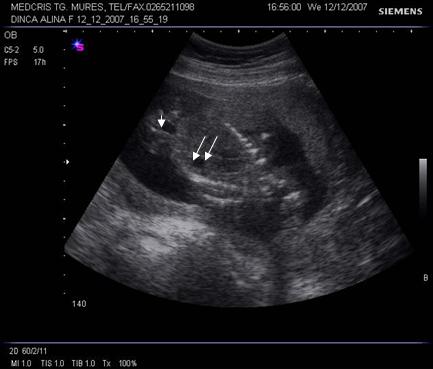

Fig. nr.177. Planul 1 de sectiune, cu imaginea de inima in 4 camere.